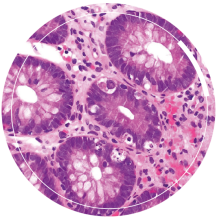

Comprendre le fonctionnement du microbiote intestinal et de ses communautés microbiennes est source de solutions favorables à un meilleur état de santé. L’intestin est le lieu où agissent les pré-, pro- ou post-biotiques : des aliments favorisant la diversité du microbiote tels que les fibres, des microorganismes enrichissant le microbiote comme les ferments, ou encore des molécules d’intérêt fonctionnel issues de microorganismes. L’intestin dialogue avec le cerveau, ce qui potentialise le rôle du microbiote intestinal vers d’autres cibles métaboliques et influence positivement son fonctionnement.

Nos solutions pour une alimentation santé ciblent un microbiote intestinal sain et diversifié, grâce à des recommandations adaptées, des pré- et probiotiques, et dès demain des médicaments issus du microbiote.